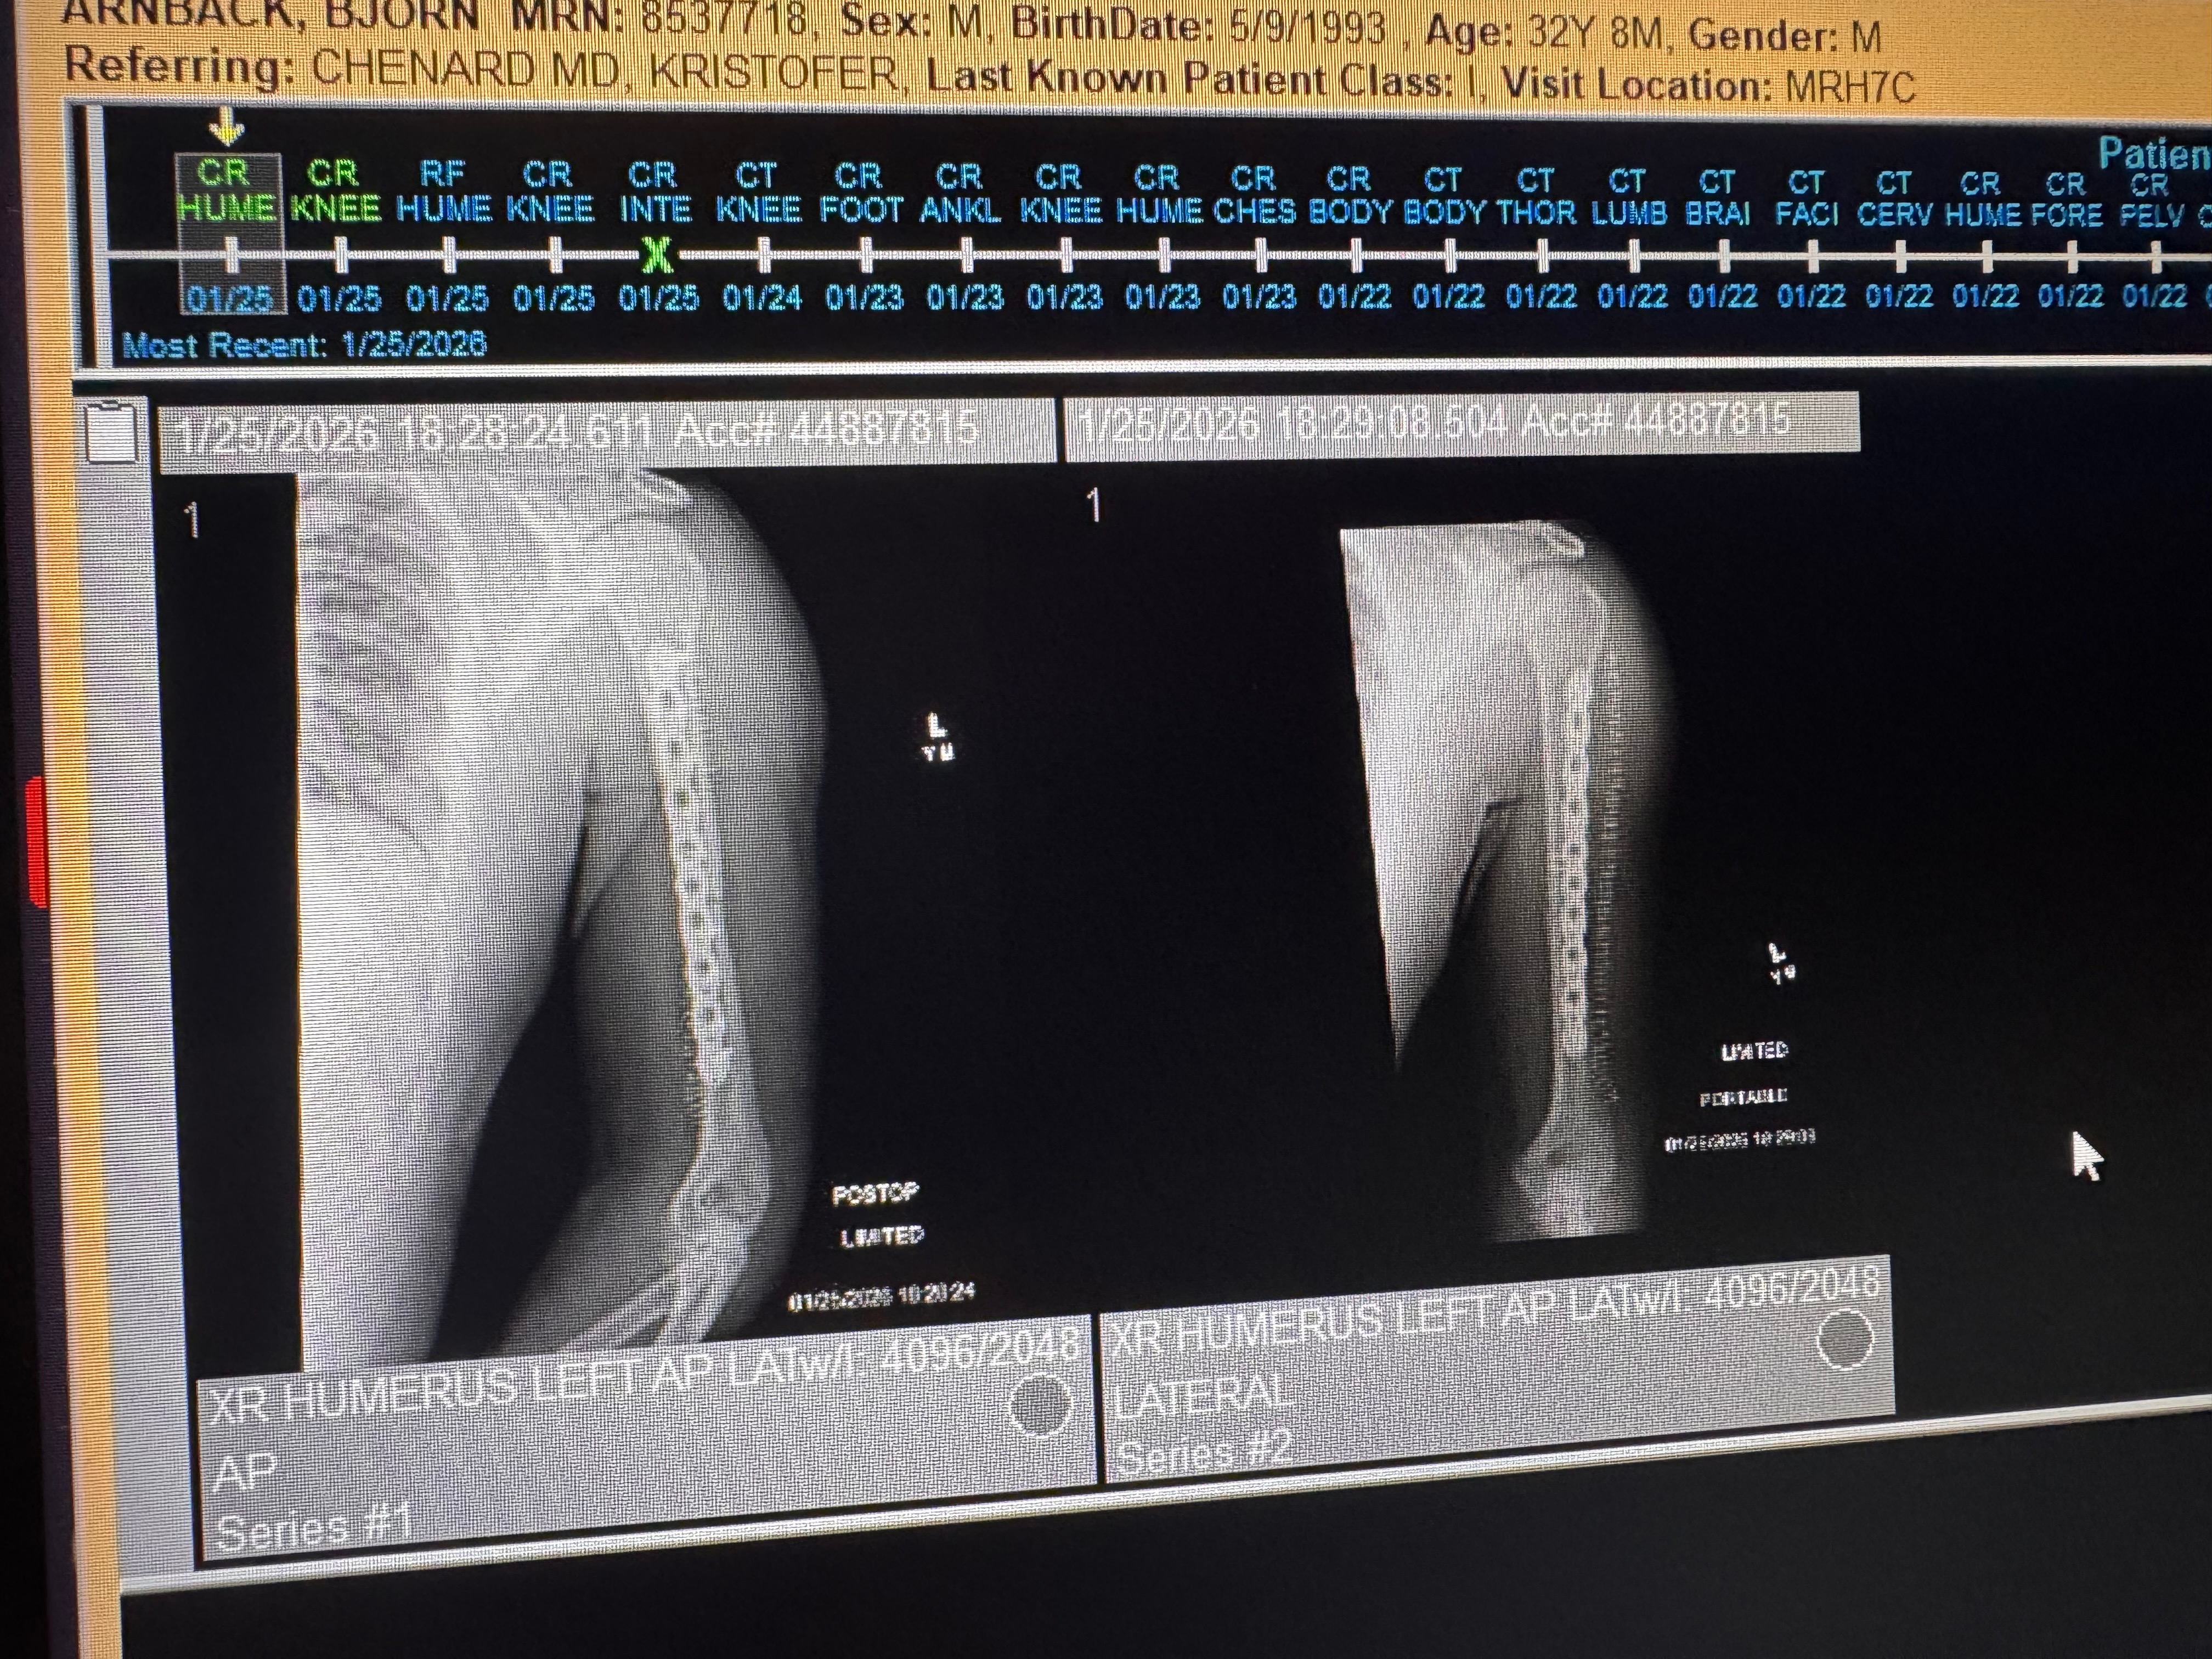

My name is Bjorn, and I’m reaching out because I recently experienced a life-changing motorcycle accident. In an instant, my world was turned upside down when I snapped my arm and broke my knee. The pain and shock were overwhelming, and I’m now facing a long and difficult recovery.